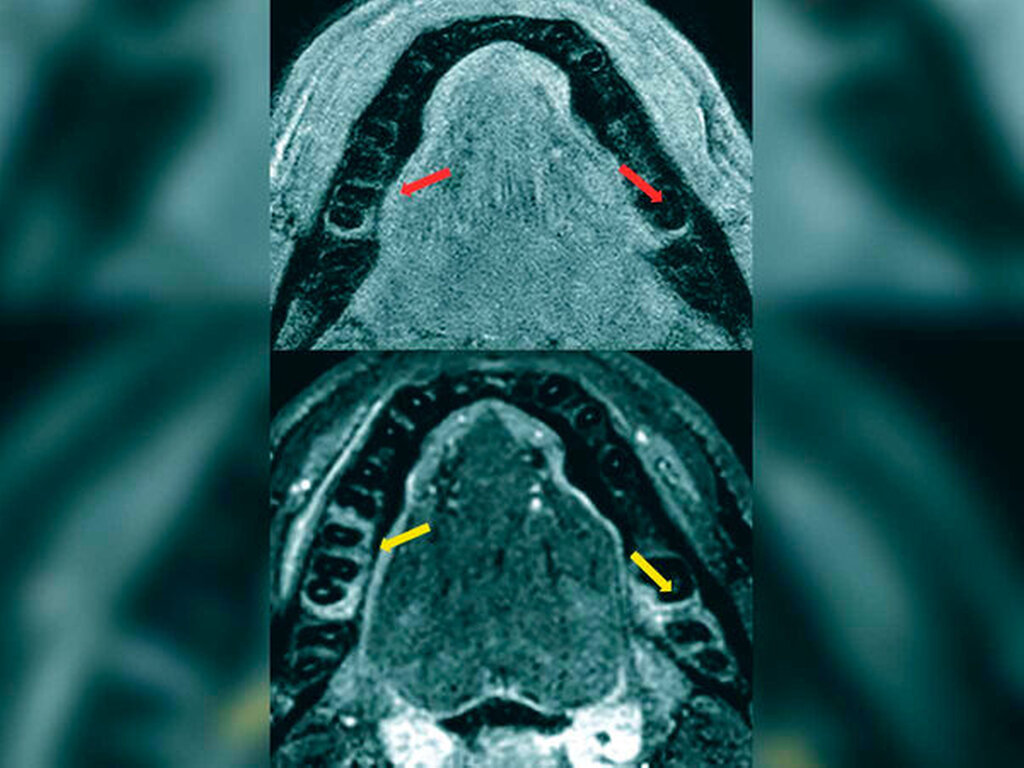

Die Auswertung des Knochenverlusts ergab einen Unterschied zwischen den Werten, die in der OPT gemessen wurden, und denen aus den MRT-Aufnahmen von circa vier Prozent. Es besteht jedoch nur eine begrenzte Vergleichbarkeit der beiden Bildgebungsmodalitäten, da es sich beim Verfahren der OPT-Bildgebung um ein zweidimensionales Verfahren mit zusätzlichem Verzerrungsfaktor und bei der MRT um ein dreidimensionales Schnittbildverfahren handelt. Besser wäre der Vergleich MRT zu DVT gewesen, der uns leider nur sehr vereinzelt vorlag (Abbildungen 2 und 3).

Die MRT-Signalwerte in den Ödemsequenzen (3D STIR) bei den Kontrollpersonen und den Parodontitispatienten wurden verglichen, wobei sich ein hochsignifikanter Unterschied zwischen beiden Gruppen fand. Bei den Parodontitispatienten waren die Werte mehr als doppelt so hoch wie in der Kontrollgruppe, was den visuellen Bildeindruck messtechnisch bestätigte. In der Gruppe der Parodontitispatienten wurde das visuell detektierte Ödem durch zwei Radiologen (einen Neuroradiologen mit mehr als zehn Jahren Berufserfahrung und einen Radiologen, gleichzeitig Zahnarzt, mit fünf Jahren Berufserfahrung) vermessen. Es zeigte sich eine sehr gute Übereinstimmung zwischen den beiden Befundenden (ICC = 0,994, p < 0,0001), so dass hier valide, reproduzierbare Werte vorliegen.

Die Patientenkohorte wurde entsprechend der gemessenen Taschensondierungstiefe eingeteilt in ≤ 3 mm und > 3 mm. Die Größe des knöchernen Ödems an Stellen mit Taschensondierungstiefen, die einen gesunden (≤ 3 mm) und einen pathologischen Zustand (> 3 mm) repräsentieren, war hoch signifikant unterschiedlich (p < 0,0001). Die lineare Ausdehnung des Knochenödems wurde mit zunehmender Taschentiefe intensiver. Die Größenausdehnung des Knochenödems korrelierte signifikant mit der Taschensondierungstiefe (rho = 0,556; p < 0,0001) sowie mit einer Blutung bei Sondierung (rho = 0,264; p < 0,0001). Wenn man das ossäre Ödem als von Knochenabbau gefährdetes Areal betrachtet, ergab sich zu dem bereits stattgefundenen Knochenverlust ein zusätzlicher präklinischer Knochenverlust von 38 bis 89 Prozent. Eine Untergruppenanalyse, wobei nur die Zahnstellen mit einer Sondierungstaschentiefe ≤ 3 mm ausgewertet wurden, ergab ein signifikant stärkeres Knochenödem an Stellen mit (0,37 ± 1,01 mm) als ohne (0,22 ± 0,91 mm; p < 0,0001) Blutung bei der Sondierung. Das Zeichen der Blutung bei Sondierung korrelierte signifikant mit präklinischen Veränderungen im Alveolarknochen, nämlich einem 2,51-fach höheren Risiko für ein Knochenödem an Stellen, die positiv auf Blutung bei Sondierung waren (OR 2,51; 95 Prozent CI: 1,54–4,11; p < 0,0001).

Anders als die konventionelle Röntgenaufnahme basiert die Magnetresonanztomografie (MRT) auf nicht-ionisierender Strahlung und nutzt die unterschiedlichen magnetischen Eigenschaften der in Wasser und Fett enthaltenen Wasserstoffkerne zur Bildgebung. Aufgrund der Anreicherung von freiem Wasser im Extrazellulärraum entzündeter Knochenbereiche kann die MRT das daraus resultierende Knochenödem darstellen [McGonagle et al., 1998]. Die Kombination von 3-D-T1-Knochensequenzen und 3-D-T2-STIR-Sequenzen zeigt zuverlässig Knochenabbau und von Abbau gefährdeten Knochen an. Es finden sich diverse Studien in der Literatur, die alle zu dem Ergebnis kommen, dass die T1-Knochensequenzen vergleichbare Ergebnisse liefern wie CT-Scans [Breighner et al., 2018; Cho et al., 2019; Gersing et al., 2019; Ruetters et al., 2019; Juerchott et al., 2020]. Die T2-STIR-Sequenz grenzt aktive entzündliche knöcherne Läsionen zuverlässig ab [Baraliakos et al., 2005]. Stellen mit einer klinischen Sondierungstiefe von ≤ 3 mm werden im Allgemeinen mit einem gesunden Zahnhalteapparat assoziiert [Chapple et al., 2018]. Interessanterweise fanden sich jedoch in der MRT auch knöcherne Ödeme an Stellen mit Sondierungstiefen von 2 oder 3 mm. Insbesondere zeigte eine spezifische Analyse der Daten mit einer Sondierungstiefe ≤ 3 mm einen klaren Zusammenhang zwischen dem Vorhandensein eines Knochenödems und der Manifestation von Blutungen bei der Sondierung. Diesen Daten zufolge ist das Risiko für das Auftreten eines Knochenödems innerhalb des zahntragenden Knochens an Stellen mit Sondierungsblutungen 2,5-mal höher als bei negativem Blutungszeichen.